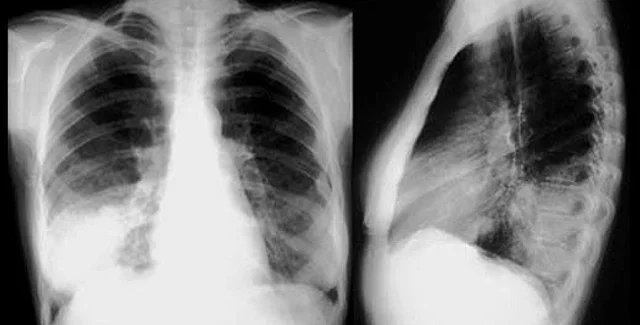

Сымитировать действие легкого, но уже в миниатюрном устройстве на основе микрочипа, также удалось Дональду Ингберу из Гарвардского университета и его коллегам: устройство размером со стирательную резинку, по их мнению, может стать полезным инструментом для тестирования новых лекарств и решения других задач.

"Способность "легкого на чипе" поглощать наночастицы в воздухе и имитировать воспалительную реакцию на патогенных микробов представляет собой принципиальное доказательство того, что органы на микрочипах могут в будущем заменить лабораторных животных", - сказал Ингбер.

Ученые смоделировали устройство стенки альвеолы, легочного пузырька, через который осуществляется газообмен с капиллярами. Для этого они высадили на синтетическую мембрану с одной стороны клетки эпителия из альвеол человеческого легкого, а с другой - клетки легочных сосудов. К клеткам легкого в устройстве подается воздух, к "сосудам" - жидкость, имитирующая кровь, а периодическое растяжение и сжатие передает процесс дыхания.

Чтобы проверить, насколько хорошо устройство имитирует реакцию легких на различные воздействия, ученые заставили его "вдохнуть" бактерии группы кишечных палочек (Escherichia coli). Бактерии попали на "легочную" сторону с воздухом, и в то же время со стороны "сосудов" исследователи пустили в поток жидкости белые кровяные клетки. Клетки легкого обнаружили присутствие бактерии и запустили иммунный ответ: лейкоциты перешли через мембрану на другую сторону и уничтожили чужеродные организмы.

Ученые также добавили в воздух, "вдыхаемый" аппаратом, различные наночастицы, в том числе типичные загрязнители воздуха. Некоторые виды этих частиц попали в легочные клетки и вызвали воспаление, а многие свободно прошли в "кровоток". При этом ученые обнаружили, что механическое давление при дыхании существенно усиливает поглощение наночастиц, что их коллеге, Бенджамину Мэтьюсу, впоследствии удалось подтвердить в эксперименте на мышах.